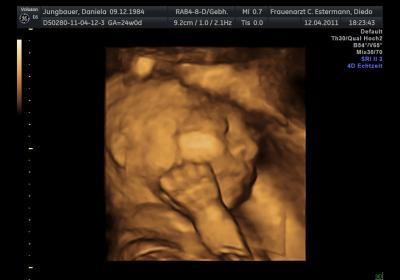

Die Wade von unserem feschen Mädel!!!

Bild zu